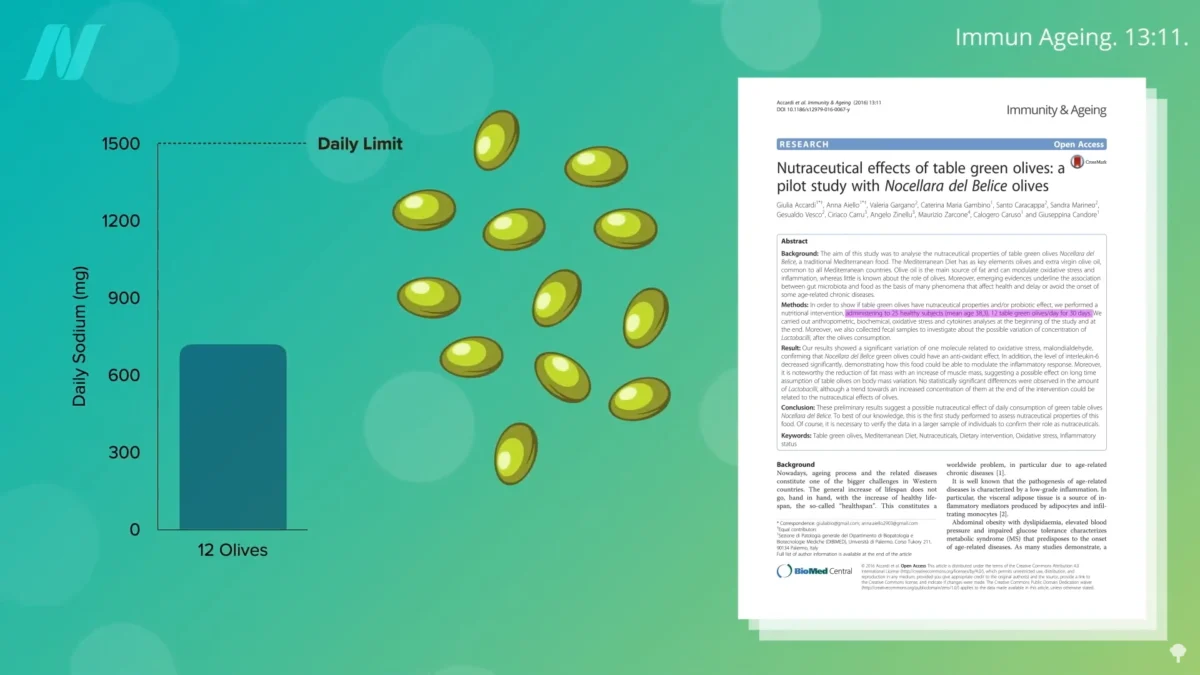

Onions: Unpacking the Evidence from Randomized Human Trials for Health Benefits

Onions, a staple in kitchens worldwide and a cornerstone of countless culinary traditions, have long been lauded for their potential health-promoting properties. While anecdotal evidence and traditional medicine have often…